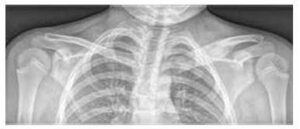

Slika 6

Ewingov sarkom, ki prizadene medenični skelet